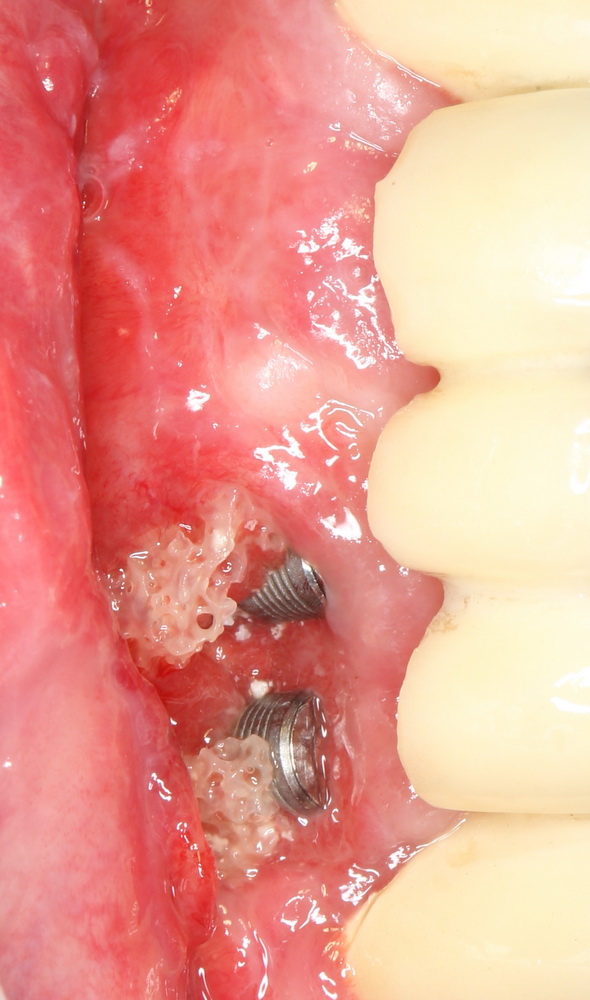

Итак, друзья, давеча мне пришлось удалить у одного пациента установленные ранее импланты одного производителя. Из одного участка зубного ряда. Одинаковым способом, а именно — специальным инструментом для удаления имплантов.

Данные импланты установили больше, чем полгода назад, после предварительной остеопластики. Они остеоинтегрировались. Но потом что-то пошло не так — и результат не устроил ни пациента, ни ортопеда, ни меня. Приходится всё удалять и переделывать.

Но вопрос не в этом. Эти два импланта на фото выше.

На ваш взгляд, какой из них пришлось выкручивать с большим усилием? Или, по-другому — какой из имплантов лучше держался в кости? И почему?

Левый или правый?